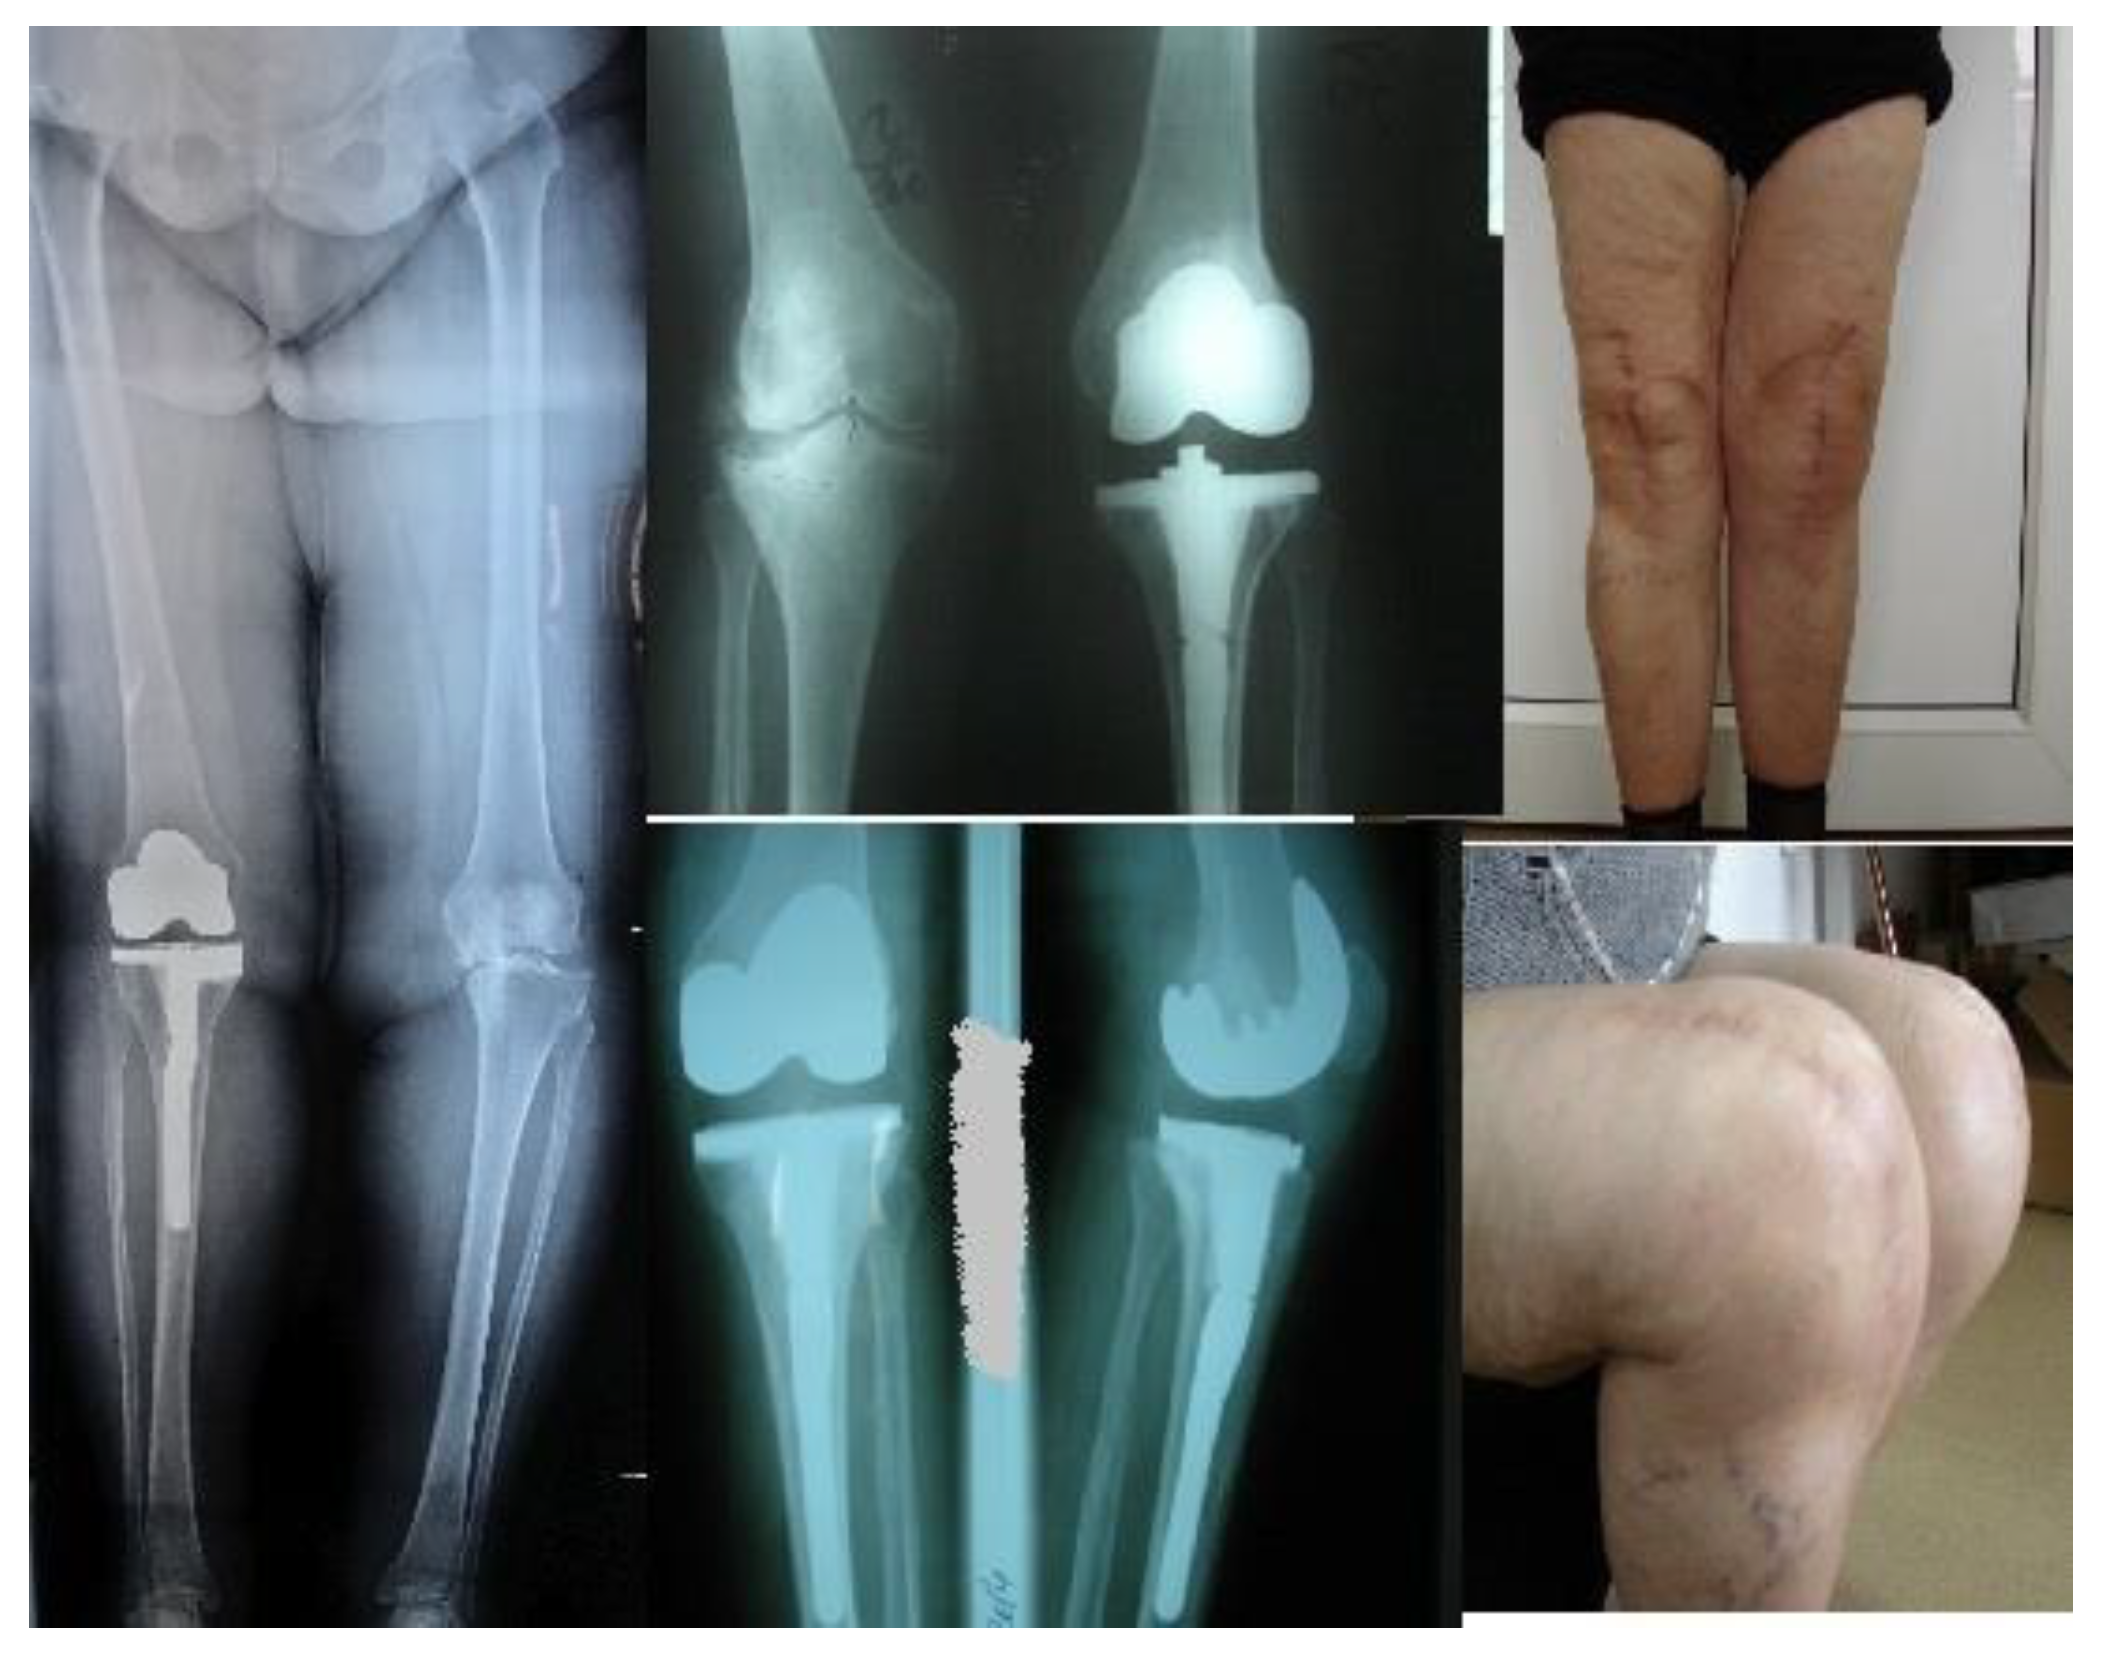

We illustrate here a primary case of TKA with valgus deformity on right knee, varus deformity on left knee - who necessitates the use of revision components with tibial stem extension with offset. (Figure 5).

Figure 5. Primary TKA with revision components tibial stem extension and offset, X-ray and clinical result.